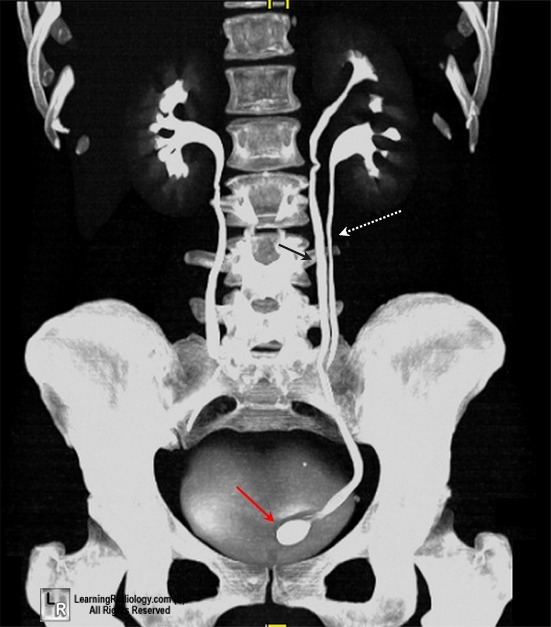

✳️التشخيص:

📌الفحص بالتصوير المقطعي المحوسب (CT)